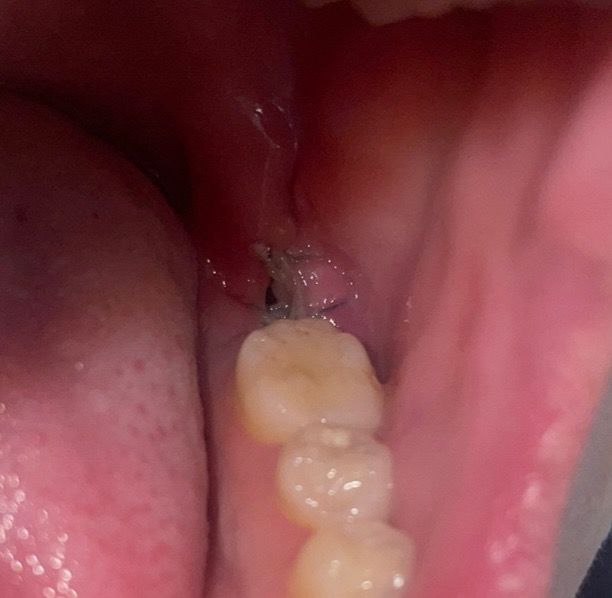

드라이소켓의심 질문자 입니다 . +사진 확인 도와주세요

사진과 육안으로 너무 선명한 구멍이 보입니다ㅜㅜ 분명 수술 이후 2-3일동안 이렇게 큰 구멍이 보이지는 읺았던거 같아서요.

• 1번 째 사진

드라이소켓의 양상 아닙니다 발치 후 저정도 구멍 있는건 지극히 정상입니다 구멍이 온전히 메워지기 위해서는 한달이상 걸립니다

원래 치아 발치후에는 발치한 자리에 이정도의 구멍은 생깁니다. 통증이 더 심해지면 치과로 도로 가서 확인하고 필요한 치료해야 합니다. 사진으로 보기에는 드라이소켓 같지는 않습니다.